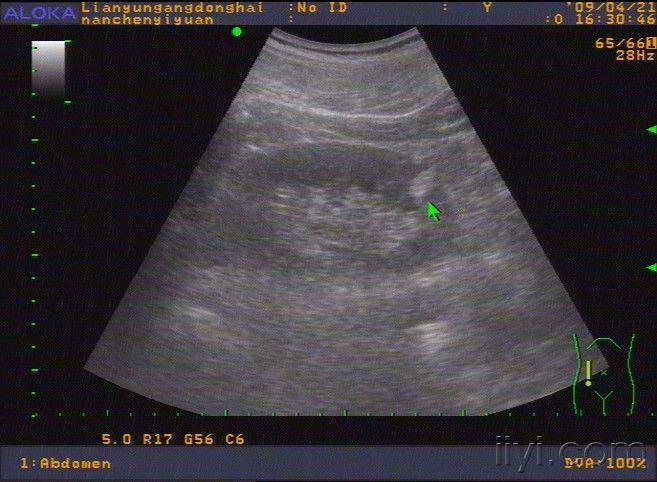

肾错构瘤 超声

肾错构瘤2例. - 超声医学讨论版 - 爱爱医医学论坛